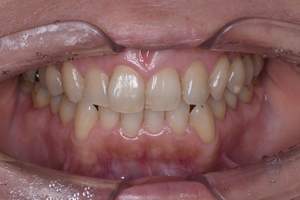

治療前

治療後

| 年齢 | 25歳・男性 |

| 主訴 | 歯石をとりたい・検診 |

| 治療内容 | 各種検査・歯石除去 |

| 治療期間 | 60分 |

| 費用 | 初診料3,000〜4,000円前後 +歯石除去約1,000円 |

| リスク・副作用 | ・処置後に歯がしみることがあります。 ・歯と歯の間に隙間ができるので、息が漏れ発音しにくいと感じることがあります。 ・歯ぐきの炎症が軽減すると歯ぐきが引き締まり、歯が長く見えることがあります。 |

| 担当者所見 | 前歯の裏側にすぐに歯石が溜まってしまいザラザラして気になるとご相談いただいたので適切な歯ブラシの当て方とフロスの通し方をお伝えさせて頂きました。 |